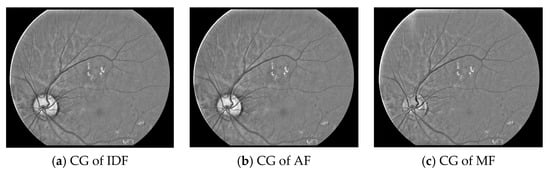

Then, the equalized channels undergo histogram stretching to improve the contrast of the ROI. This step generates contrast-adjusted blue, red and green channels denoted as CB(x,y), CR(x,y) and CG(x,y). Figure 4 shows the CG(x,y) of the image in Figure 1 obtained from the three filters. In most instances, histogram stretching does not affect the equalized channels much since they already have good contrast.

Figure 4. The contrast-adjusted green (CG) channels obtained from the three filters.